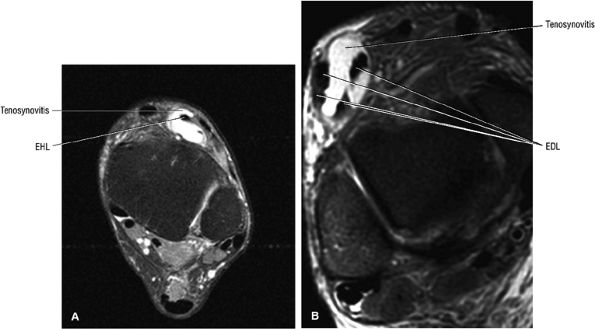

The anterior muscles of the leg are the tibialis anterior (Fig. 5.2), the extensor hallucis longus (Fig. 5.3), the extensor digitorum longus (Fig. 5.4) and the peroneus tertius (Fig. 5.5).

![]() |

|

FIGURE 5.3 ● EXTENSOR HALLUCIS LONGUS Extensor hallucis (and extensor digitorum) injuries are similar in origin to injuries of the tibialis anterior tendon. Extensor hallucis longus (EHL) paratenonitis is associated with pain and swelling localized to the ankle joint with painful resisted extension of the hallux. The EHL extends the great toe and dorsiflexes the foot.

FIGURE 5.4 ● EXTENSOR DIGITORUM LONGUS Extensor digitorum longus (EDL) paratenonitis is associated with pain and swelling over the ankle joint and lateral to the extensor hallucis longus. There is pain with resisted extension of the lesser toes in paratenonitis. The EDL extends the phalanges of the lateral four toes and dorsiflexes the foot.